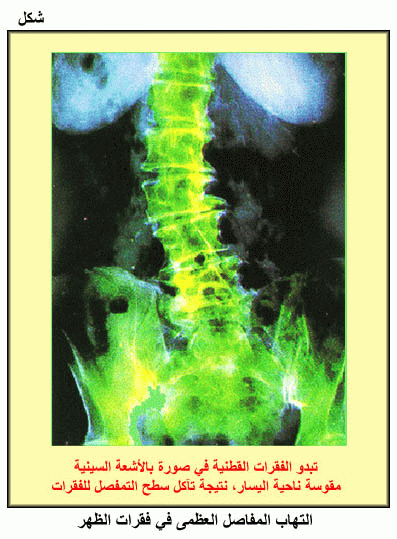

التهاب المفاصل العظمى في فقرات الظهر